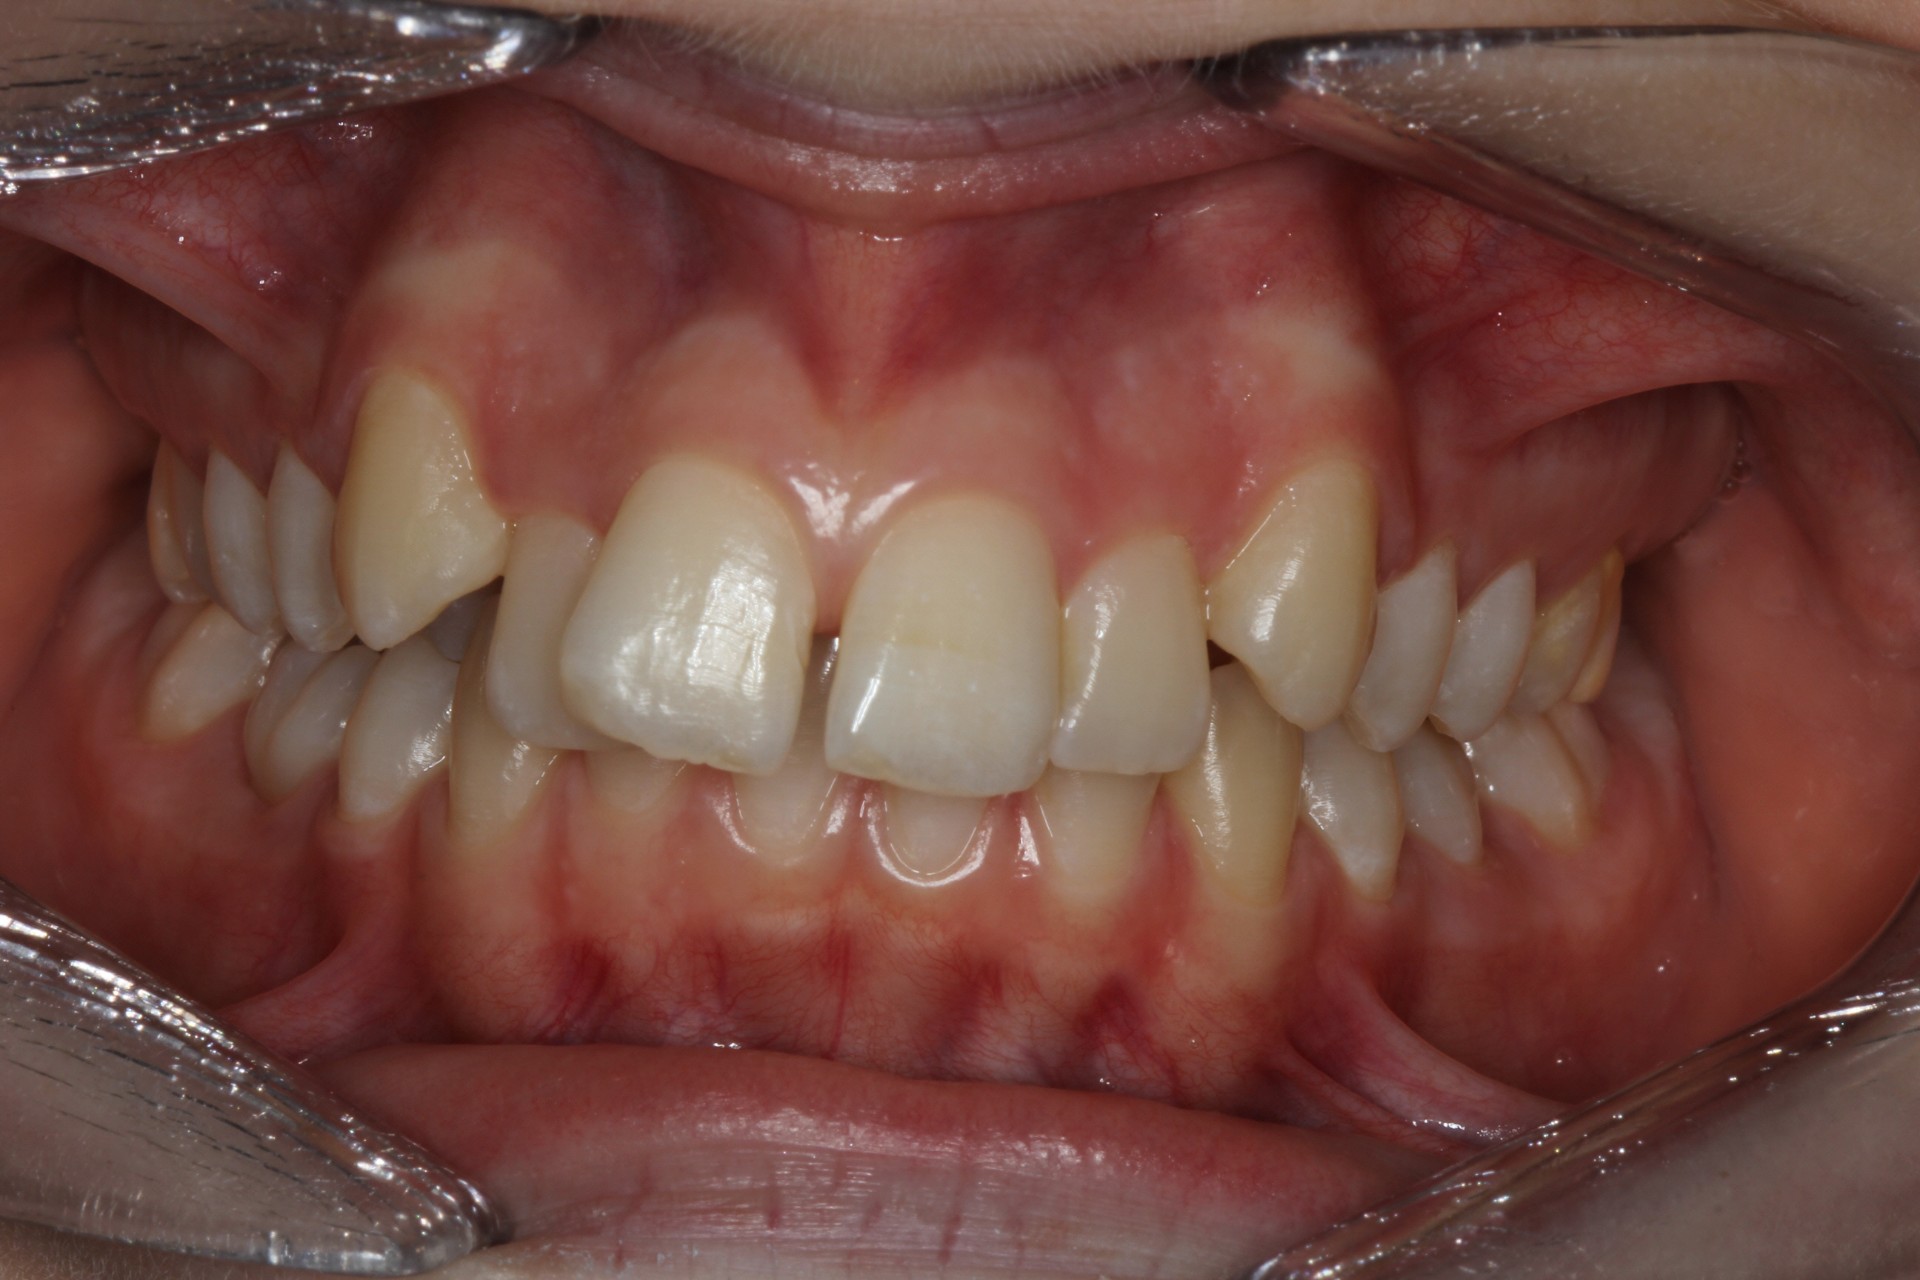

Protruding front teeth – Child case